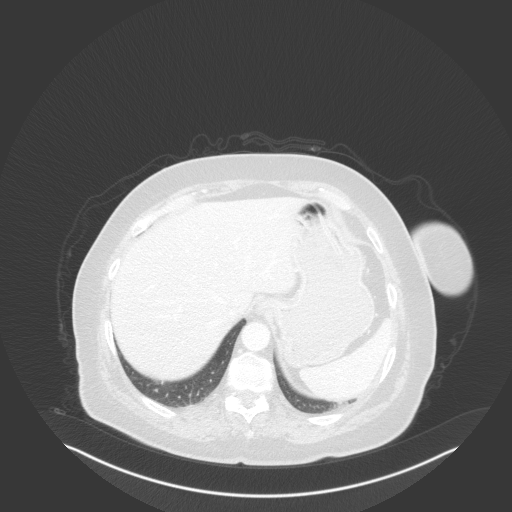

Generated VENOUS CT scan (A→B translation)

No window - Raw intensity values

Lung window (WL -600, WW 1500 β†’ Low βˆ’1350, High +150)

Mediastinum window (WL 40, WW 400 β†’ Low βˆ’160, High +240)